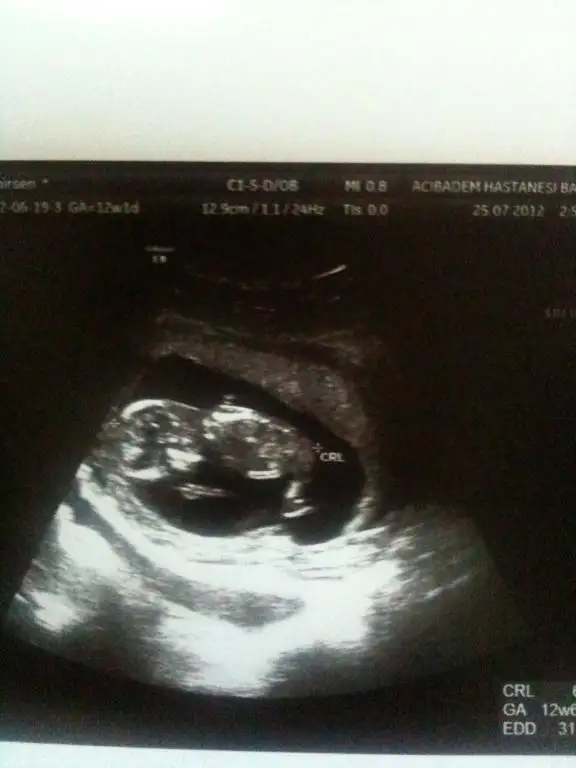

ORKDM bu benim bebişimin 12+1 günlük fotoları. ne dersin tahmin için uygun mu? bi el atsan